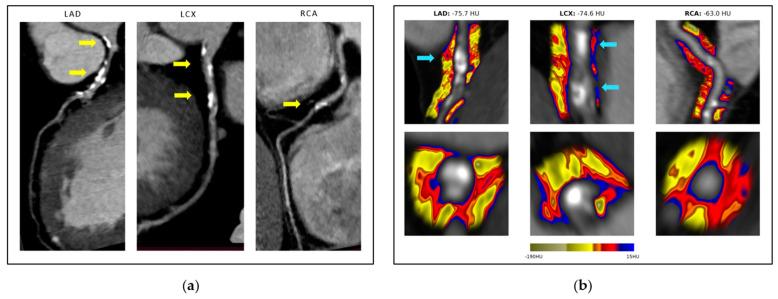

Inflammation is a key factor in the development of atherosclerosis, a disease characterized by the buildup of plaque in the arteries. COVID-19 infection is known to cause systemic inflammation, but its impact on local plaque vulnerability is unclear. Our study aimed to investigate the impact of COVID-19 infection on coronary artery disease (CAD) in patients who underwent computed tomography angiography (CCTA) for chest pain in the early stages after infection, using an AI-powered solution called CaRi-Heart. The study included 158 patients (mean age was 61.63 ± 10.14 years) with angina and low to intermediate clinical likelihood of CAD, with 75 having a previous COVID-19 infection and 83 without infection. The results showed that patients who had a previous COVID-19 infection had higher levels of pericoronary inflammation than those who did not have a COVID-19 infection, suggesting that COVID-19 may increase the risk of coronary plaque destabilization. This study highlights the potential long-term impact of COVID-19 on cardiovascular health, and the importance of monitoring and managing cardiovascular risk factors in patients recovering from COVID-19 infection. The AI-powered CaRi-Heart technology may offer a non-invasive way to detect coronary artery inflammation and plaque instability in patients with COVID-19.

炎症是动脉粥样硬化发展的一个关键因素,动脉粥样硬化是一种以动脉斑块积聚为特征的疾病。已知 COVID-19 感染会引起全身炎症,但它对局部斑块脆弱性的影响尚不清楚。我们的研究旨在使用名为 CaRi-Heart 的人工智能解决方案,调查 COVID-19 感染对感染后早期接受计算机断层扫描血管造影 (CCTA) 检查胸痛的冠心病 (CAD) 患者的影响。该研究纳入了 158 名(平均年龄为 61.63 ± 10.14 岁)有胸痛且 CAD 临床可能性低至中度的患者,其中 75 名患者以前感染过 COVID-19,83 名患者没有感染。结果表明,以前感染过 COVID-19 的患者的冠状动脉周围炎症水平高于没有 COVID-19 感染的患者,这表明 COVID-19 可能增加冠状动脉斑块不稳定的风险。这项研究强调了 COVID-19 对心血管健康的潜在长期影响,以及在 COVID-19 感染后康复的患者中监测和管理心血管危险因素的重要性。基于人工智能的 CaRi-Heart 技术可能为检测 COVID-19 患者的冠状动脉炎症和斑块不稳定性提供一种非侵入性的方法。